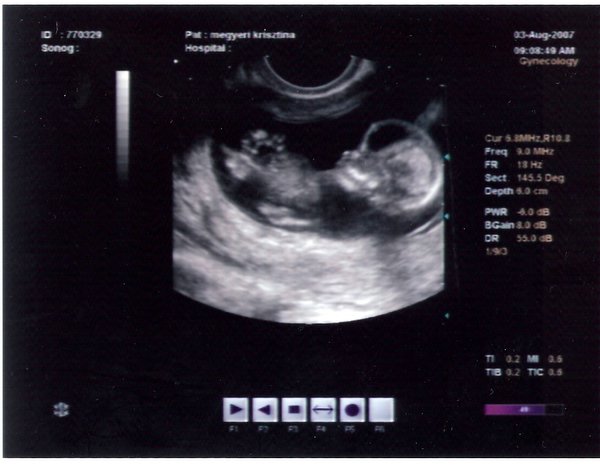

Én ma megjártam az Uh-t, ahol 2 órát csücsültem

sajna képet nem kaptam, még a sima feket is 1000Ft lett volna

Viszont a pincurral minden rendben van. Találkoztam a szülészdokival is, ő is nagyon szimpi és kedves volt. Utána irány a város másik vége bel. Na ott 3. alkalomra sikerült megcsinálniuk a leletet, nem akartam aludni